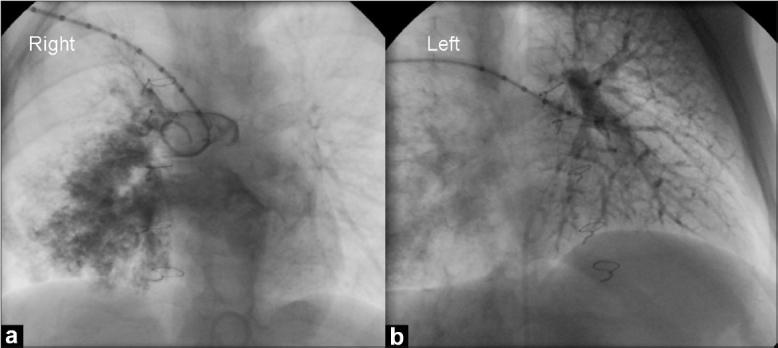

Pulmonary arteriovenous malformation (PAVM) is common after cavopulmonary anastomosis. PAVMs appear on chest X-ray film as diffuse opacity in one or both lungs. Angiographically, it appears as spidery diffuse vascularity with near simultaneous opacification of pulmonary arteries and veins.